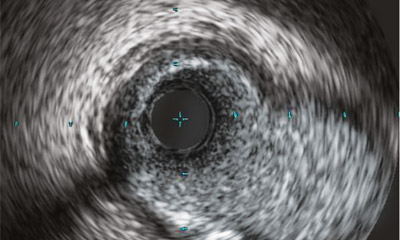

IVUS- und Physiologie Workshop

WORKSHOP

IVUS

Mehr Informationen

IVUS Workshop

IVUS: Grundlagen und Einsatz im Alltag eines Herzkatheterlabors

Workshops Clock Icon image

Dauer: 1 Tag

Termine 2023:

28.04.

03.11.

Workshops Community Icon image

Teilnehmer:

optimal 8-10 Personen

Trainer Icon

Fachexperten:

PD Dr. Moritz Seiffert

Dr. med. Fabian J. Brunner

Locator Icon image

Ort:

Hamburg